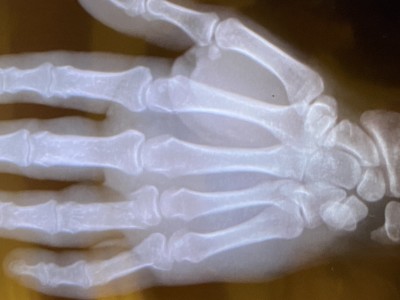

491Zet'm op! Alle tijd nu voor reflectie, als je dat al niet deed. Beterschap!

Sterkte Frans.